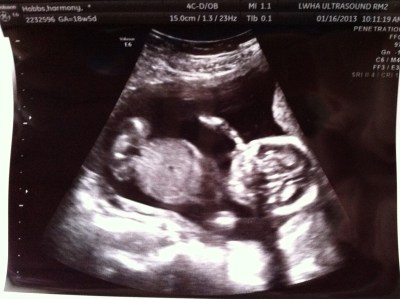

Meet THREE. My daughter.

WE’RE HAVING A GIRL!

The ultrasound tech wasn’t able to get a clear picture of the baby, because she was super wiggly and appeared to be trying to shimmy up the walls of my uterus to escape the ultrasound waves. Despite the appearance of this not-very-good photo, she is perfectly developed with all of her limbs proportioned and her major organs fully in tact.